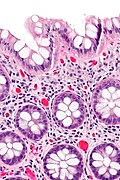

Microscopic

Features:

- Test tube like glands.

- Minimal palisading.

- Nuclei <3:1 = height:width.

- No nuclear pseudostratification. †

- Deep part of crypt is more hyperchromatic than superficial component - important.

- The surface should be lighter staining than the deeper aspect, i.e. the deeper glands are dark blue and the superficial gland are light blue.

Images

- Rectum - low mag.jpg

Rectum - low mag. (WC)

- Rectum - intermed mag.jpg

Rectum - intermed. mag. (WC)

- Rectum - alt - intermed mag.jpg

- Rectum - high mag.jpg

Rectum - high mag. (WC)